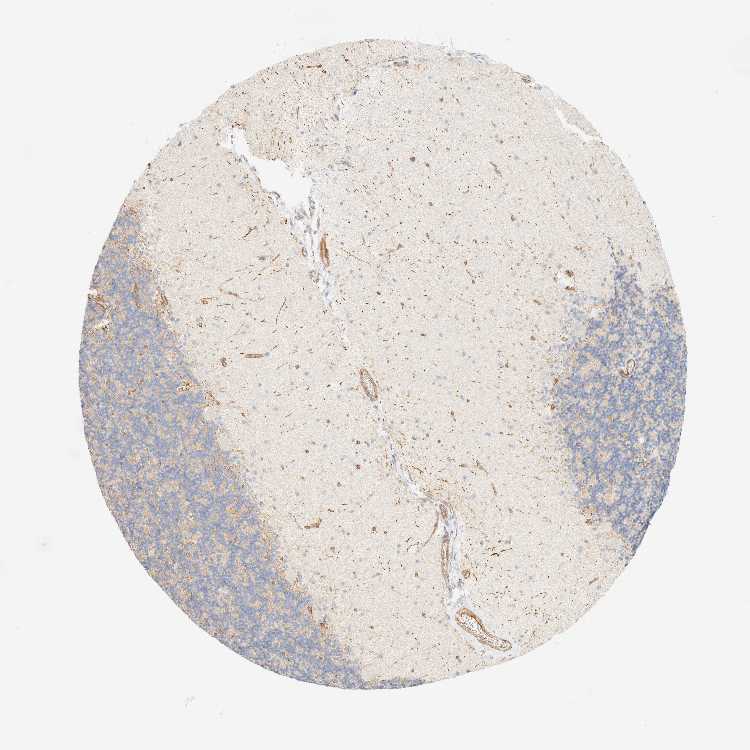

CEREBELLUM - Antibody stainingi

Antibody staining in the annotated cell types in the current human tissue is reported as not detected, low, medium, or high, based on conventional immunohistochemistry profiling in selected tissues. This score is based on the combination of the staining intensity and fraction of stained cells.

Each image is clickable and will lead to virtual microscopy that enables deeper exploration of all samples and also displays staining intensity scores, fraction scores and subcellular localization as well as patient and tissue information for each sample.

Antibody HPA024524Antibody HPA053090

Purkinje cells Not detectedNot detected

Cells in granular layer LowLow

Cells in molecular layer LowNot detected